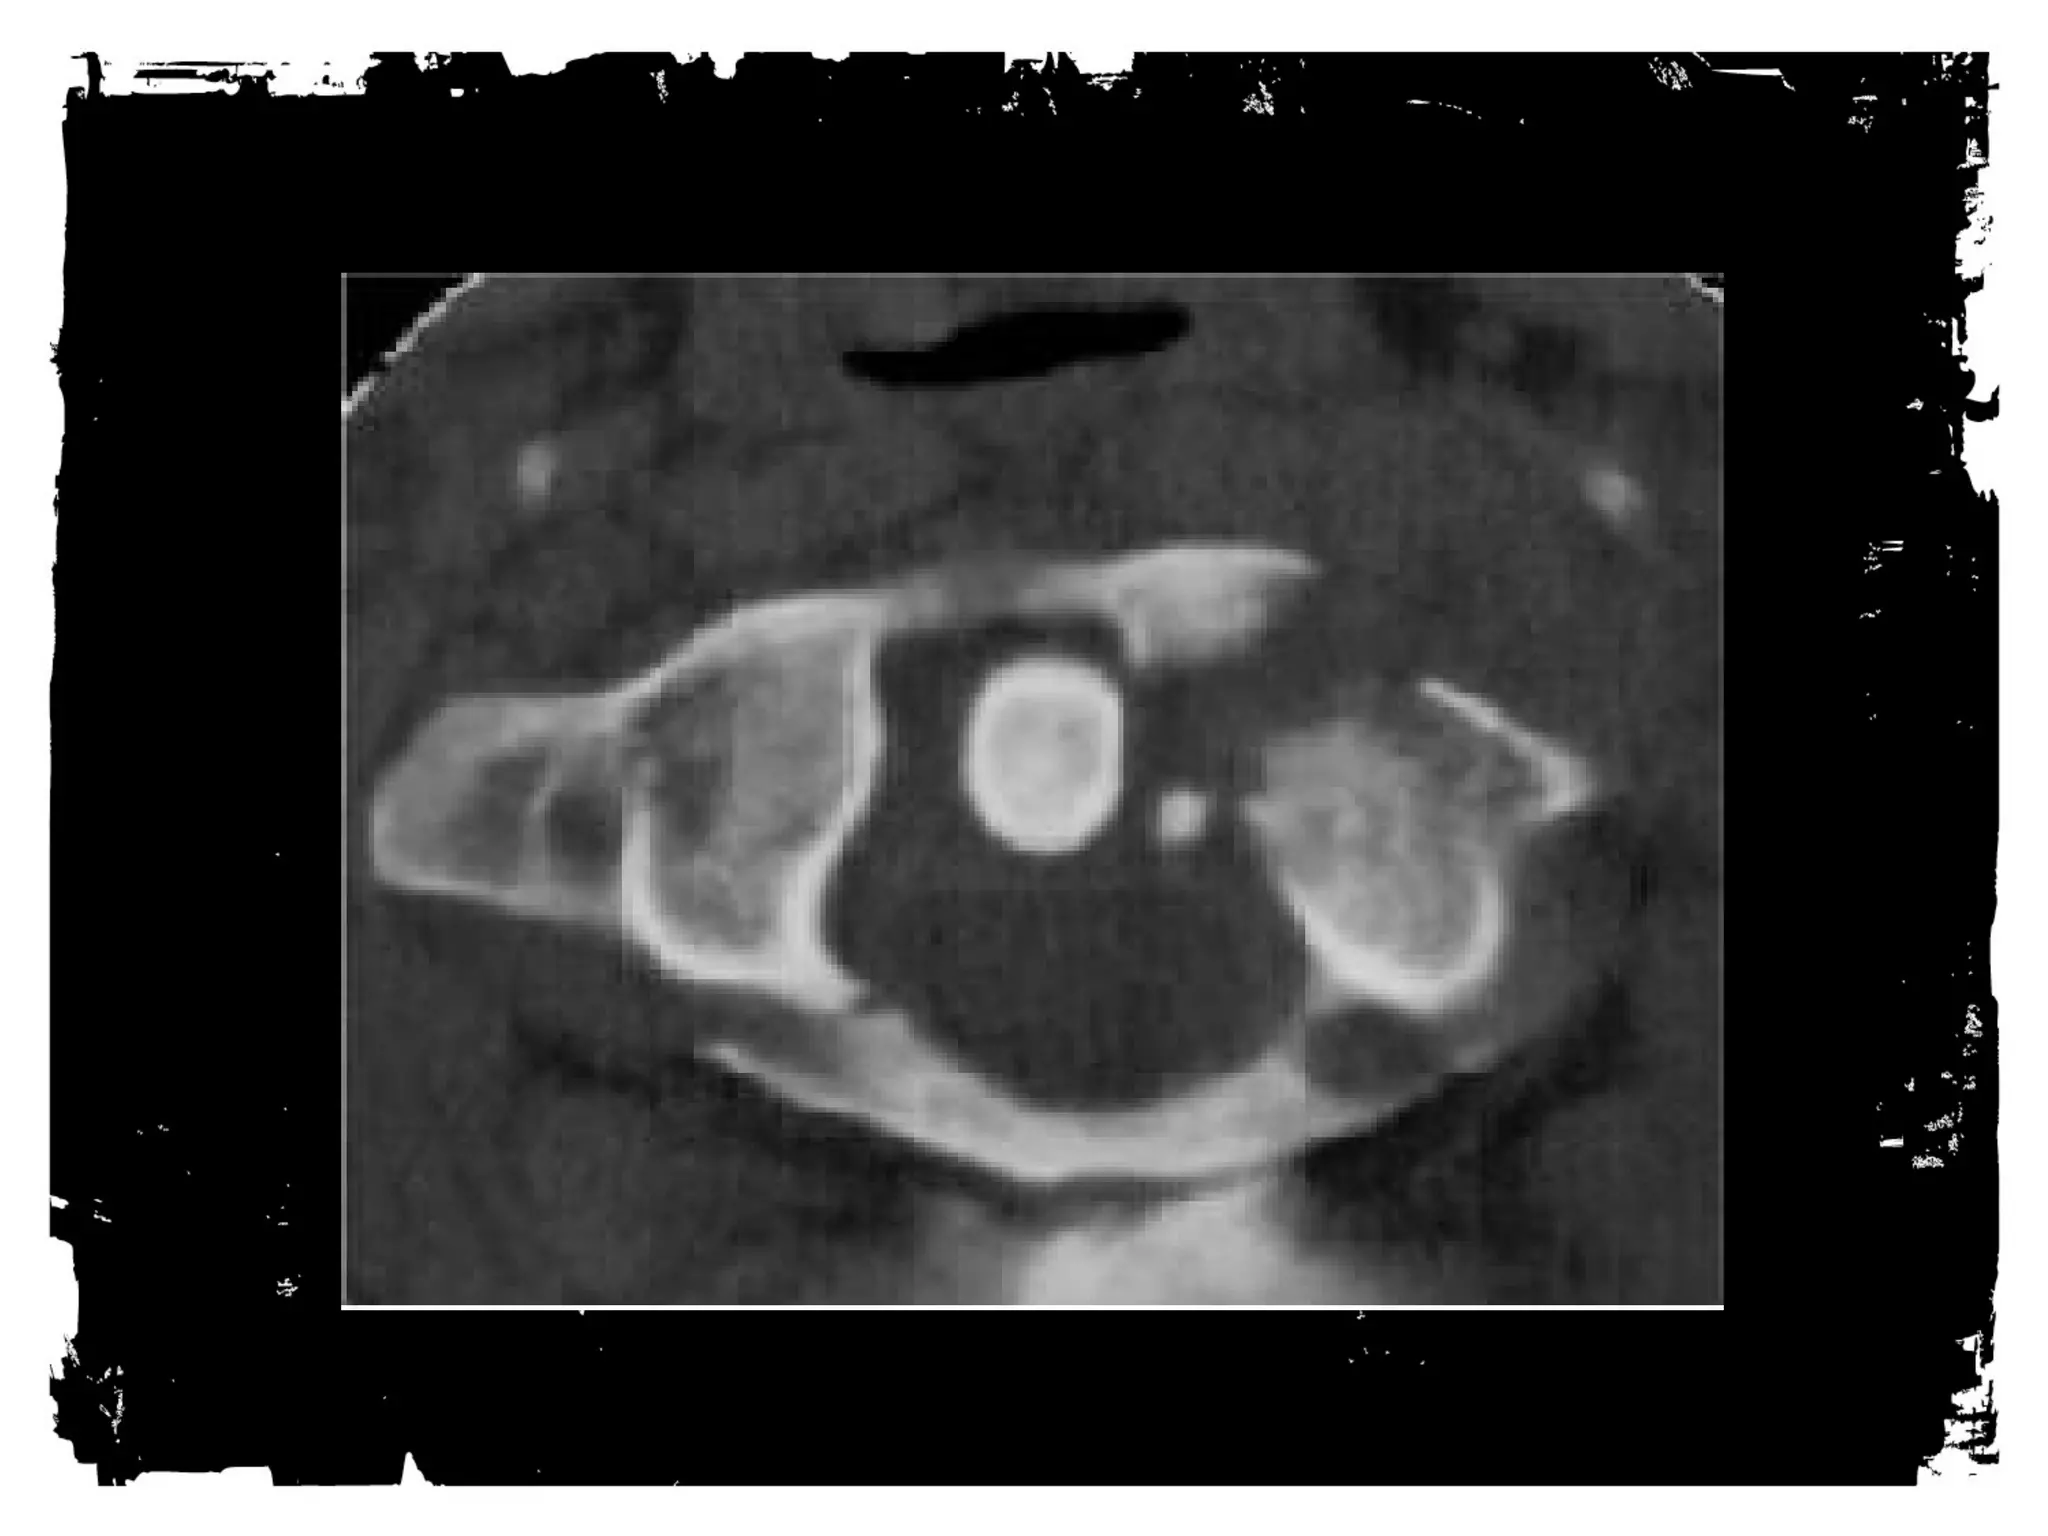

Sterno-Clavicular Dislocations

• Anterior: Not much of a

problem.

• Posterior: Less common; can

injure great vessels or trachea.

Sterno-clavicle dislocation: CT